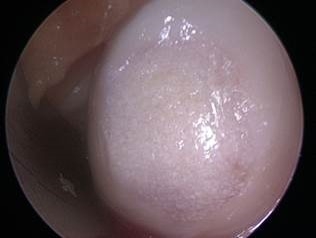

Articular Cartilage Defect

Cartilage defect of medial femoral condyle